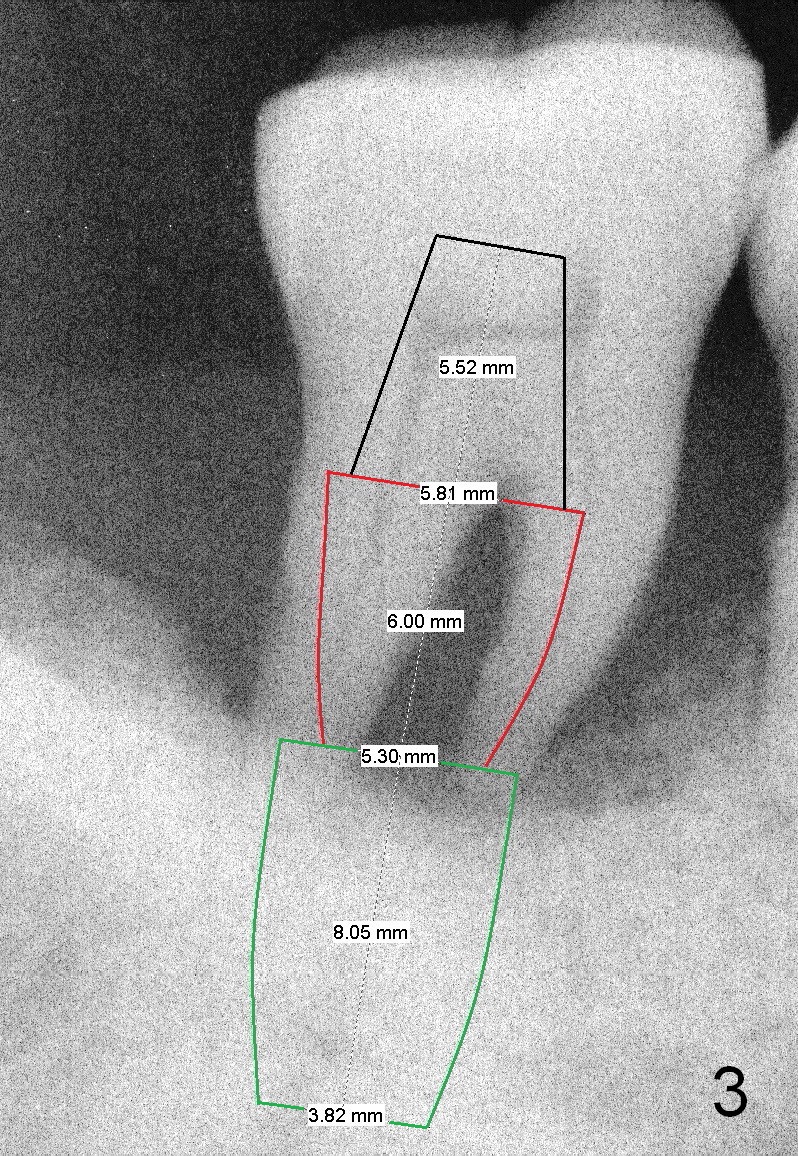

A 46-year-old lady has generalized moderate localized severe (Fig.1 (panorex) #31) chronic periodontitis.  Surprisingly there is sufficient bone height (Fig.1 white dashed line: upper border of the Inferior Alveolar Canal).  The gingiva is quite thick (Fig.2 (PA) arrowheads: gingival margin).  In order to prevent thread exposure associated with immediate implant, a bone-level implant will be placed (Fig.3 5.3x8 mm; green lines) with a long abutment (5.8x5.5 mm (black lines) (6 mm cuff; red lines)).   Initial osteotomy depth is between 14 and 17 mm.  Insert a parallel pin and take the 1st intraop PA.  Use reamers to enlarge osteotomy and collect autogenous bone.  A drill with a stopper (5x8mm) will be used prior to placement of the implant mentioned above.  Since the opposing is a removable partial denture, an immediate provisional at the site of #31 should be safe to be fabricated.  Bone graft will be placed to cover the exposed implant surface.  The remaining gap will be filled with collagen dressing and the provisional.  A temporary abutment is the other option.  The shoulder of the temporary abutment will be subgingival to long extent.  Is the plan well executed?